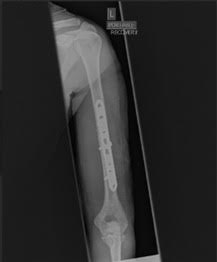

Ma la rivoluzione “Smart Hospital” non si ferma alla struttura! C’è un’altra parte del progetto che è altrettanto spaziale: l’utilizzo del Deep Learning per la diagnostica delle immagini! Immaginate: un’intelligenza artificiale che analizza i raggi X e ti dice se c’è una frattura ossea in un batter d’occhio. Sembra fantascienza, vero? E invece è già realtà!

Hanno lavorato su un dataset di raggi X dell’omero, con immagini di ossa sane e fratturate. Un po’ come insegnare a un computer a distinguere un braccio rotto da uno perfetto. Hanno fatto “runnare” questi modelli su Python, modificando i parametri per trovare l’ottimizzazione migliore. E alla fine? Il modello che si è rivelato il più performante è stato ResNet! Un vero e proprio triumfo dell’IA al servizio della salute!